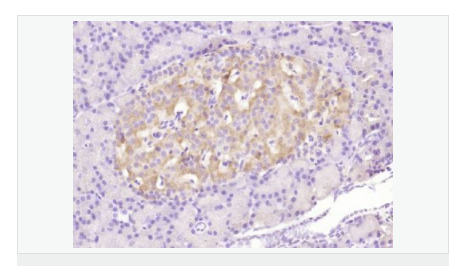

| 產(chǎn)品應用 | WB=1:500-2000 ELISA=1:5000-10000 IHC-P=1:100-500 Flow-Cyt=3μg /test (石蠟切片需做抗原修復) not yet tested in other applications. optimal dilutions/concentrations should be determined by the end user. |

| 產(chǎn)品介紹 | The protein encoded by this gene belongs to the BCL2 protein family. BCL2 family members form hetero- or homodimers and act as anti- or pro-apoptotic regulators that are involved in a wide variety of cellular activities. This protein forms a heterodimer with BCL2, and functions as an apoptotic activator. This protein is reported to interact with, and increase the opening of, the mitochondrial voltage-dependent anion channel (VDAC), which leads to the loss in membrane potential and the release of cytochrome c. The expression of this gene is regulated by the tumor suppressor P53 and has been shown to be involved in P53-mediated apoptosis. Multiple alternatively spliced transcript variants, which encode different isoforms, have been reported for this gene. [provided by RefSeq, Jul 2008]. Function: Accelerates programmed cell death by binding to, and antagonizing the apoptosis repressor BCL2 or its adenovirus homolog E1B 19k protein. Under stress conditions, undergoes a conformation change that causes translocation to the mitochondrion membrane, leading to the release of cytochrome c that then triggers apoptosis. Promotes activation of CASP3, and thereby apoptosis. Subunit: Homodimer. Forms higher oligomers under stress conditions. Interacts with BCL2L11. Interaction with BCL2L11 promotes BAX oligomerization and association with mitochondrial membranes, with subsequent release of cytochrome c. Forms heterodimers with BCL2, E1B 19K protein, BCL2L1 isoform Bcl-X(L), BCL2L2, MCL1 and A1. Interacts with SH3GLB1 and HN. Interacts with SFN and YWHAZ; the interaction occurs in the cytoplasm. Under stress conditions, JNK-mediated phosphorylation of SFN and YWHAZ, releases BAX to mitochondria. Isoform Sigma interacts with BCL2A1 and BCL2L1 isoform Bcl-X(L). Interacts with RNF144B, which regulates the ubiquitin-dependent stability of BAX. Interacts with CLU under stress conditions that cause a conformation change leading to BAX oligomerization and association with mitochondria. Does not interact with CLU in unstressed cells. Interacts with FAIM2/LFG2. Subcellular Location: Isoform Alpha: Mitochondrion membrane; Single-pass membrane protein. Cytoplasm. Note=Colocalizes with 14-3-3 proteins in the cytoplasm. Under stress conditions, undergoes a conformation change that causes release from JNK-phosphorylated 14-3-3 proteins and translocation to the mitochondrion membrane. Isoform Beta: Cytoplasm. Isoform Gamma: Cytoplasm. Isoform Delta: Cytoplasm (Potential). Tissue Specificity: Expressed in a wide variety of tissues. Isoform Psi is found in glial tumors. Isoform Alpha is expressed in spleen, breast, ovary, testis, colon and brain, and at low levels in skin and lung. Isoform Sigma is expressed in spleen, breast, ovary, testis, lung, colon, brain and at low levels in skin. Isoform Alpha and isoform Sigma are expressed in pro-myelocytic leukemia, histiocytic lymphoma, Burkitt's lymphoma, T-cell lymphoma, lymphoblastic leukemia, breast adenocarcinoma, ovary adenocarcinoma, prostate carcinoma, prostate adenocarcinoma, lung carcinoma, epidermoid carcinoma, small cell lung carcinoma and colon adenocarcinoma cell lines. Similarity: Belongs to the Bcl-2 family. SWISS: Q07812 Gene ID: 581 Database links: Entrez Gene: 581 Human Entrez Gene: 12028 Mouse Omim: 600040 Human SwissProt: Q07812 Human SwissProt: Q07813 Mouse Unigene: 624291 Human Unigene: 19904 Mouse Unigene: 10668 Rat Important Note: This product as supplied is intended for research use only, not for use in human, therapeutic or diagnostic applications. |